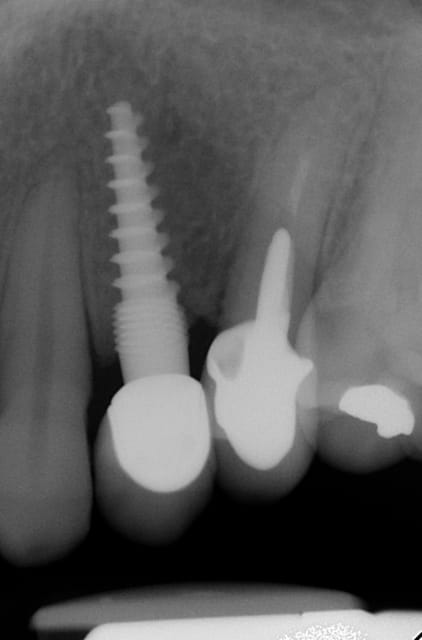

Oui,c´est un Prep cap zircone , que je cémente juste après l´implantation immédiate pour mieux former la gencive. Les implants monoblocs ont étés implantés entre 40 et 60 Ncm . Les photos 6 et 8 on voit les prep cap juste après l´implantation immédiate ce sont des sortes de "couronnes" pré fabriquées.

Oui , tu as raison pour la 45, en fait quand j´ai enlevé la 45 j´ai choisi l´axe comme ca ( dans l´os dur et en bon santé) parce que c´etait ici que je pouvais avoir la stabilité ( pour cet implant à 50 Ncm.

Voilà une patiente que je revois à deux ans apres la pose d'un monobloc Classic line 3,5/12mm et prep cap zircone 12 degres 2/2 en 24.

Radios 1,2,3 photo 1= jour de la pose de l'implant.

radio 4 photo 2 et 3= 8 semaines post pose de l'implant, ceramiques scéllées.

Radio 6, photo 4 et 5 controle à 24 mois.

Deux ans plus tard, la gencive a recouvert la zircone et on observe à la radio un gain osseux au niveau des micros spires.